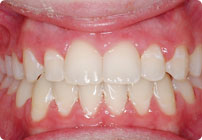

Femenino

Antes

Despues

Caso: 20 años

Adulto: Clase II,

Mordida Abierta Anterior

Sin extracción

4 series de alambres:

.016″, .022″, .0215″ x .028″, .019″ x .025″ Trenzado;

Elásticos en cajas

Triangulares TP Rosa, Verde, Azul

Retenedores: Inferior Fijo

Tiempo de tratamiento: 16 Visitas